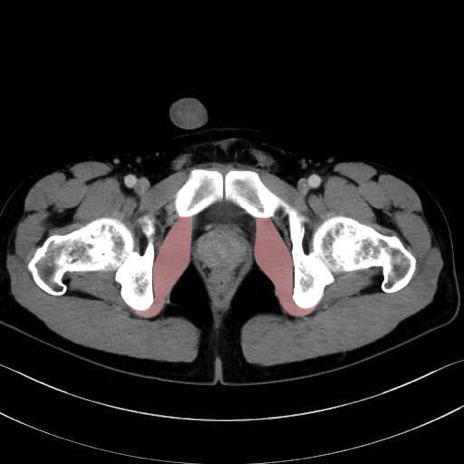

内閉鎖筋 (Obturator internus)